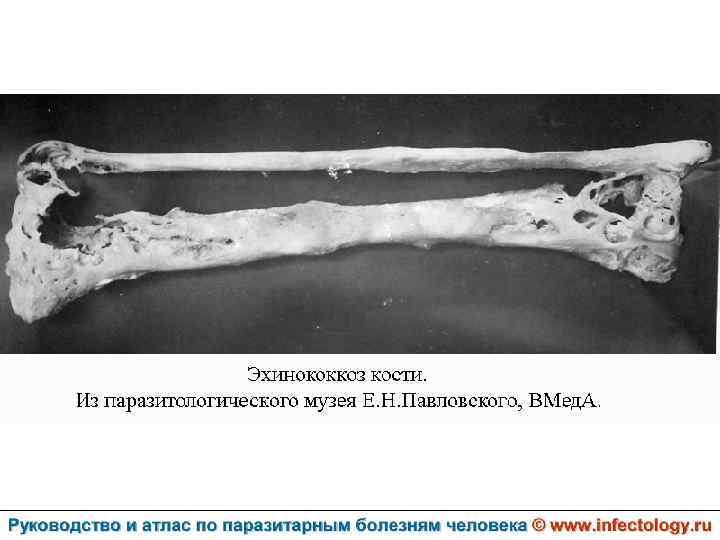

Цистный эхинококкоз (цистный гидатидоз) (шифр по МКБ 10 - B 67. 0 -4) – зоонозный биогельминтоз, характеризующийся хроническим течением, образованием кист и деструктивным поражением печени, легких и других органов.